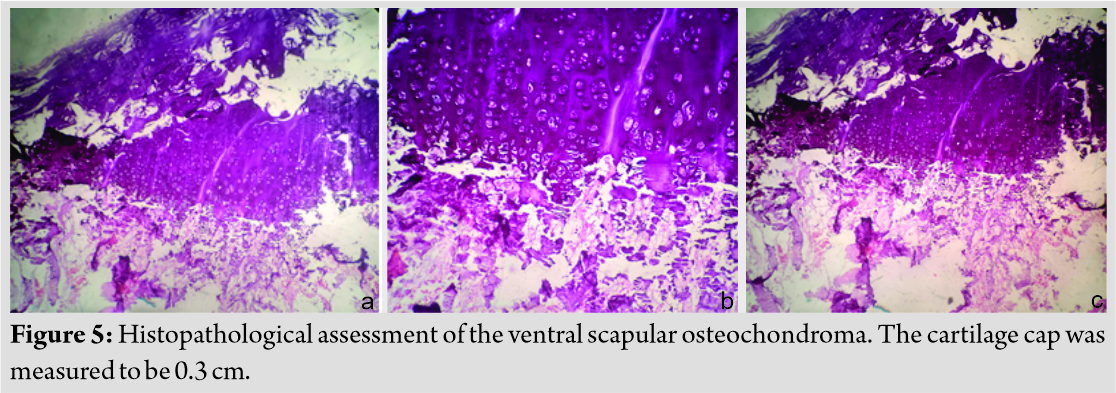

Histopathological evaluation stated that it was a tumor with a cartilage cap composed of chondrocytes in a growth plate-like pattern with an overlying fibrous perichondral and underlying fragments of trabeculae bone and bone marrow elements consistent with diagnosis of osteochondroma (Fig. 5). The cartilage cap was 0.3 cm thick on histopathological assessment. He has been free of symptoms. He has full and painless range of movements and the complete disappearance of pseudo-winging (Fig. 6). There are not any signs of recurrence so far. It has been 20 months after en bloc excision. Our plan is to follow up till skeletal maturity.

VSO is diagnosed frequently by clinical assessment and imaging, whereas confirmation is done by histopathologic evaluation [17]. VSO may be difficult to identify clinically pertaining to its location. One may miss it on plain radiographs [9]. CT or magnetic resonance imaging (MRI) helps establish a diagnosis [16]. CT scan helps in characterizing lesion and planning treatment. MRI is usually reserved for malignant transformation suspicion [14]. MRI aids in measurement cartilaginous cap thickness. A cap thinner than 1 cm usually indicates a benign lesion. Thickness of more than 2 cm generally relates to malignant change [2]. A cartilaginous cap with thickness <1 cm in biopsy indicates a benign condition, whereas a cap thicker than 2 cm should raise concern for malignant transformation [5]. In our case, the cartilaginous cap thickness was 0.3 cm.

Prognosis of single lesion is excellent [2]. Relapse is rare but occurs on leaving unclear resection margins [13]. Risk of malignant transformation is 1–2% but increases in multiple lesions [4]. Malignant transformation is estimated approximately 1% for solitary and up to 5% for multiple lesions [1]. Sarcomatous degeneration has been reported in hereditary multiple exostoses [13]. The child had a single lesion so we expect no recurrence. Growth after maturity is indicative of malignant transformation [12]. Further, cartilage cap thickness >2 cm is worrisome for malignant transformation [3]. Other signs include stippled calcification in cap, increase in size after skeletal maturity, and sudden increase in pain [17]. The histopathological assessment measured cartilaginous cap to be 0.3 cm in our patient.